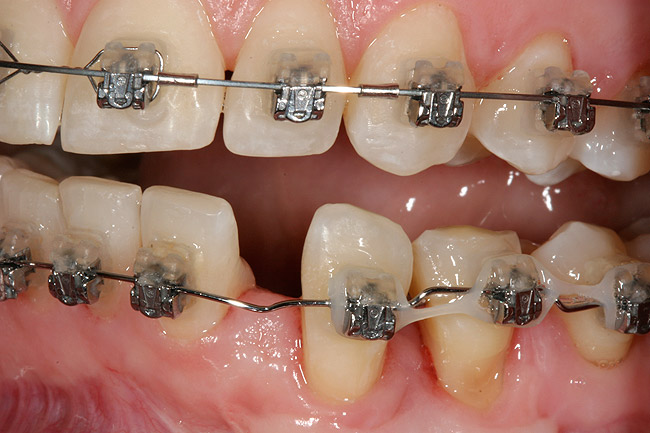

Figure 12  Right buccal view showing posterior occlusion established, canine guidance and proper space appropriation around peg lateral tooth No. 7, and intruded worn incisors.

Figure 12